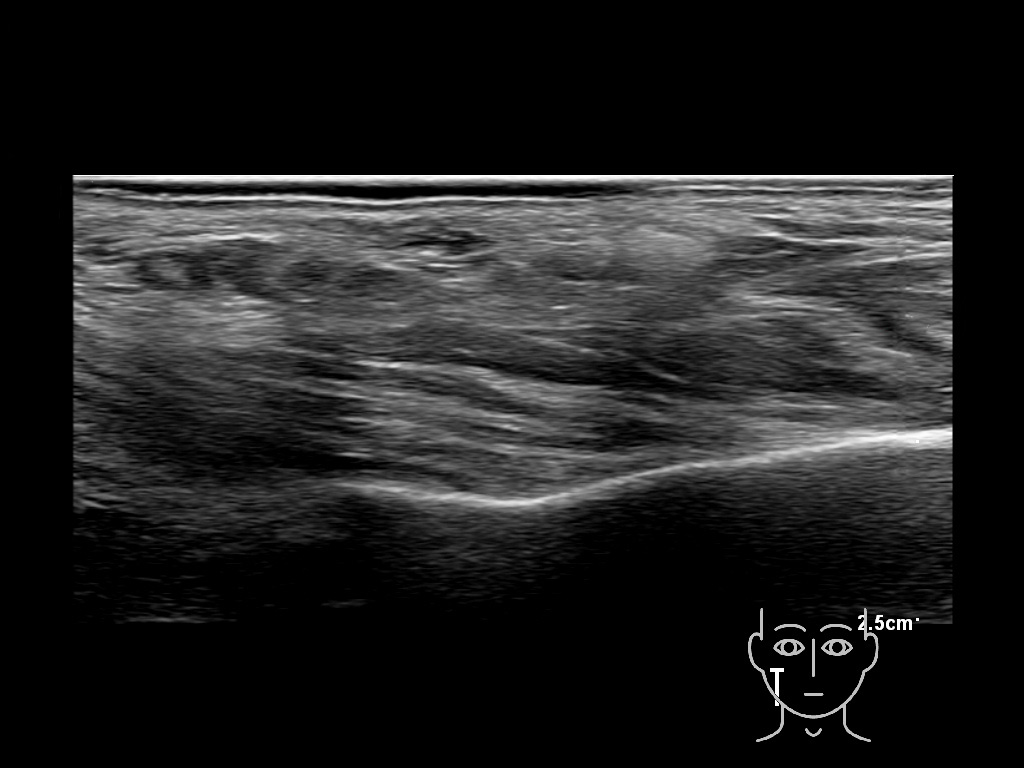

Draw in the image on the right where the fillers are located. To check if your answer is correct, please click on the secondary image.

haca 0